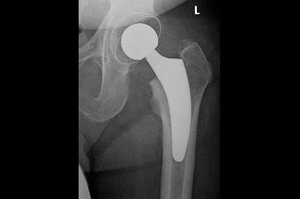

Hüft-OP zur Implantation einer Endoprothese

Bei der Operation wird zunächst der betroffene Hüftkopf am Ende des Oberschenkels entfernt. Anschließend werden sowohl die Hüftpfanne als auch der Oberschenkelknochen für die Aufnahme des Kunstgelenks präpariert.

Die einzelnen Komponenten der Hüftendoprothese werden mit dem körpereigenen Knochen der Hüfte verbunden. Grundsätzlich gibt es drei verschiedene Möglichkeiten zur Verankerung: